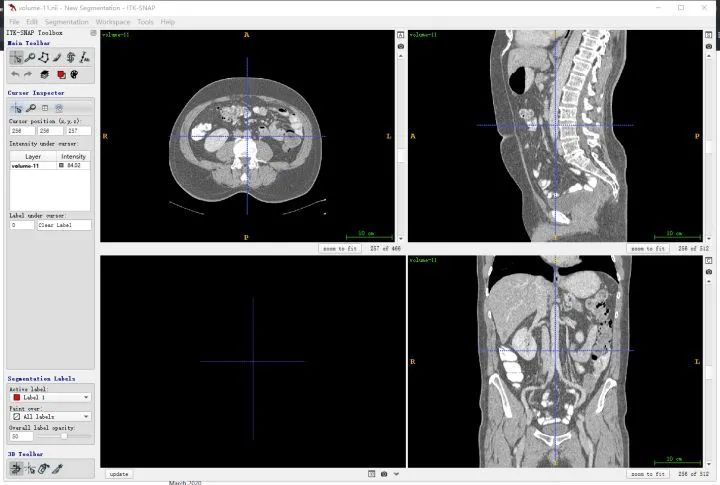

1.1 ITK-SNAP软件

首先介绍一下医学图像可视化软件ITK-SNAP, 可以作为直观感受医学图像3D结构的工具,也可以用来做为分割和检测框标注工具,免费,很好用,安利一下:ITK-SNAP官方下载地址:http://www.itksnap.org/pmwiki/pmwiki.php。此外,mangohttp://ric.uthscsa.edu/mango/是另一个非常轻量的可视化软件,也可以试试。我一般用ITK-SNAP。

ITK-snap界面

首先要明确一下和人体对应的方向,其中三个窗口对应三个切面,对应关系如下图所示,按照字母索引即可。例如,左上图对应R-A-L-P这个面,是从脚底往头部方向看的切面(即z方向),另外两张类似。

红色切面为矢状面,紫色切面为冠状面,绿色切面为横断面

也可以同时将分割结果导入,对比观察。

对于标注不太严谨的地方也可以精细化修改。当然公开集的话,绝大多数都挺好的。自己标注也是类似。(如果显示不太清晰,对比度太低,需要在软件中调节窗宽和窗位)